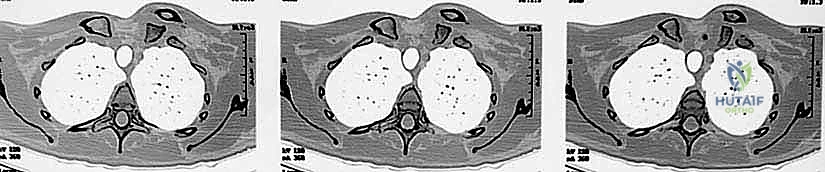

- الأشعة السينية (X-rays): يتم إجراء صور شعاعية خاصة (مثل وضعية Serendipity view). ومع ذلك، فإن الأشعة العادية غالباً ما تكون غير كافية بسبب تداخل ظلال الأضلاع والعمود الفقري مع المفصل.

- التصوير المقطعي المحوسب (CT Scan) - المعيار الذهبي: يؤكد الدكتور هطيف أن الأشعة المقطعية، خاصة مع إعادة البناء ثلاثي الأبعاد (3D Reconstruction)، هي الإجراء الحاسم. فهي تحدد بدقة متناهية اتجاه الخلع، وجود كسور مصاحبة، ومدى قرب الترقوة من الهياكل الحيوية.

- التصوير بالرنين المغناطيسي (MRI): يُستخدم في حالات محددة لتقييم الأربطة بدقة، أو في المرضى الأطفال والمراهقين لتقييم صفيحة النمو الغضروفية.